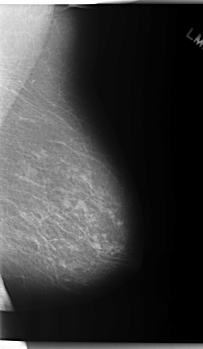

C_0254_1.LEFT_MLO

LEFT_MLO LINES 5928 PIXELS_PER_LINE 3448 BITS_PER_PIXEL 12 RESOLUTION 50 NON_OVERLAY